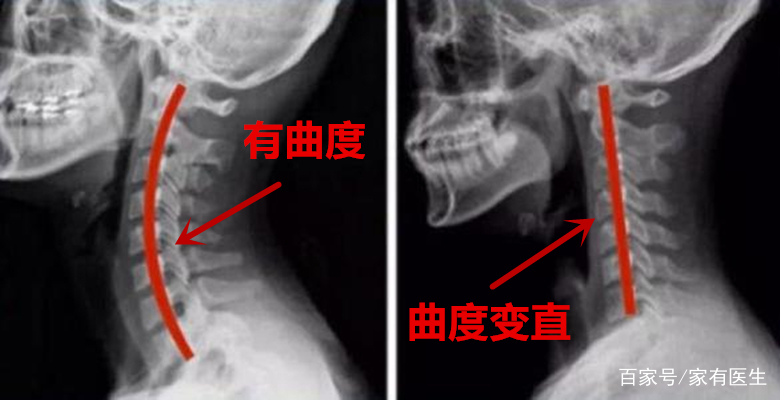

上述这些方法适合颈椎生理弧度变直甚至消失的人,这样做能够纠正颈椎的生理弧度,如果疼痛或其他不适症状有所改善,那么可以适当增加频率以及时长,如果做完之后并不舒服,甚至症状更为严重应及时停止。